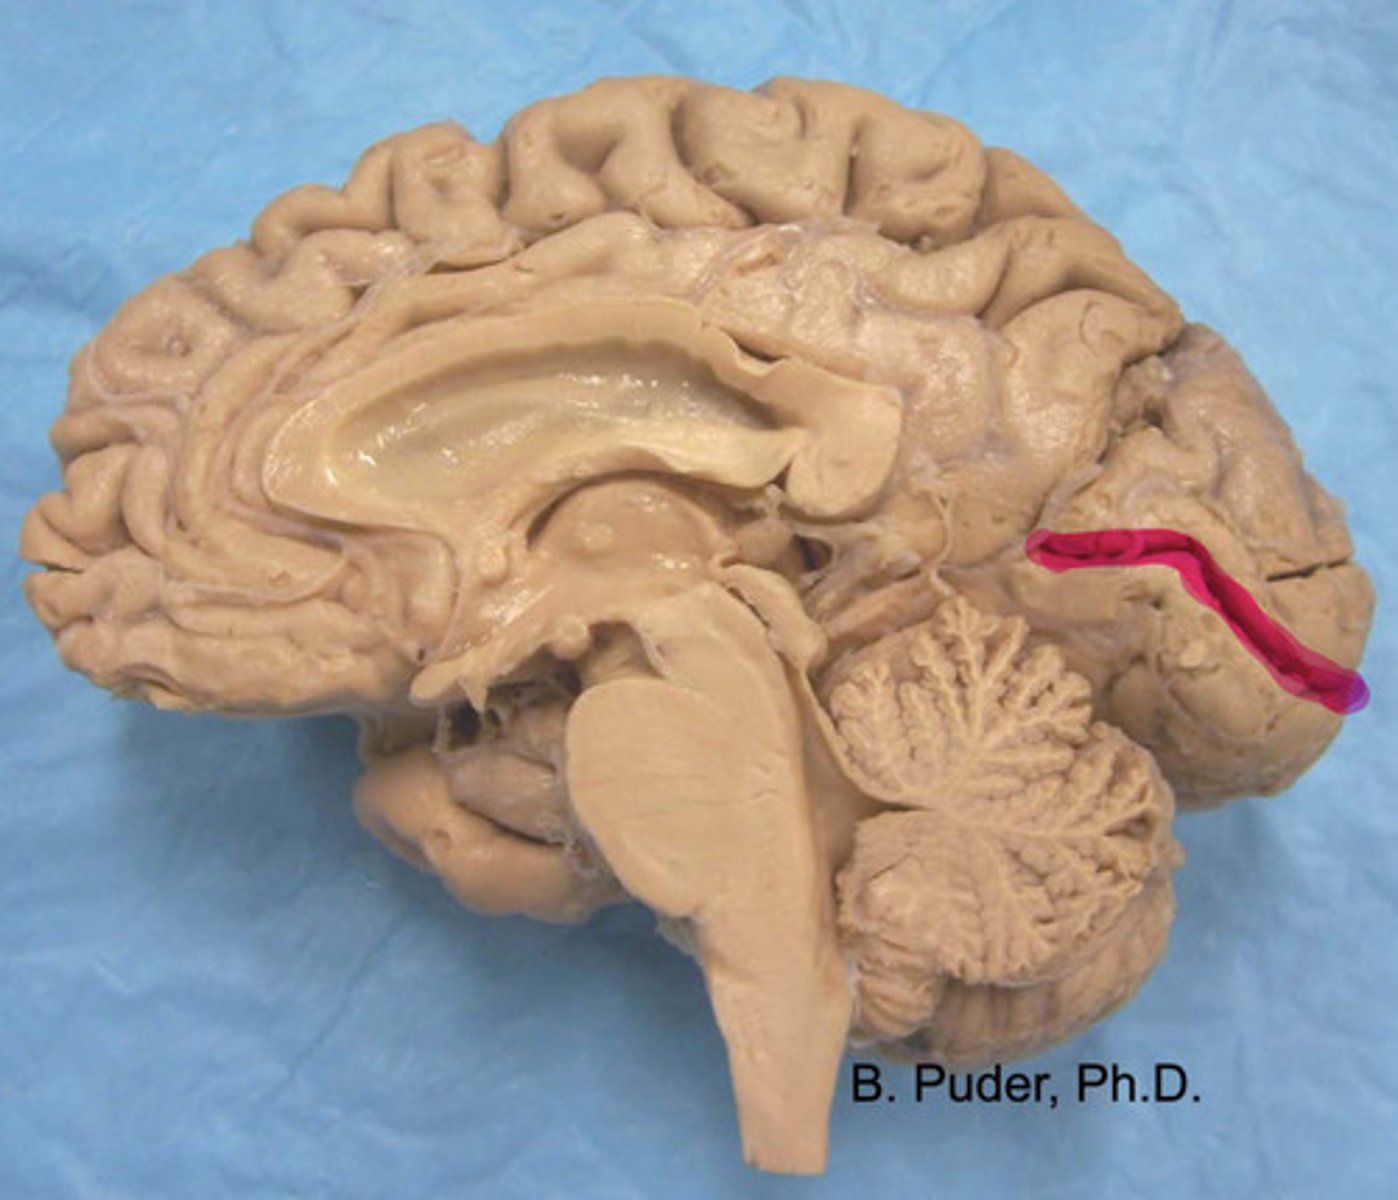

calcarine fissure

what is highlighted?